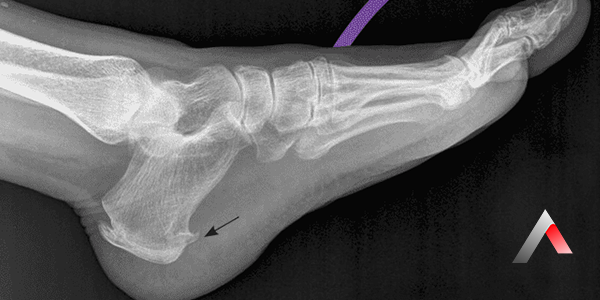

Cerrahi Tedavi (Nadir Durumlarda):

• Konservatif tedavilere rağmen ağrının geçmediği ve hastanın yaşam kalitesinin ciddi şekilde etkilendiği nadir durumlarda cerrahi tedavi düşünülebilir.

• Cerrahi seçenekler arasında plantar fasyanın bir kısmının serbest bırakılması veya kemiksi çıkıntının alınması yer alabilir.